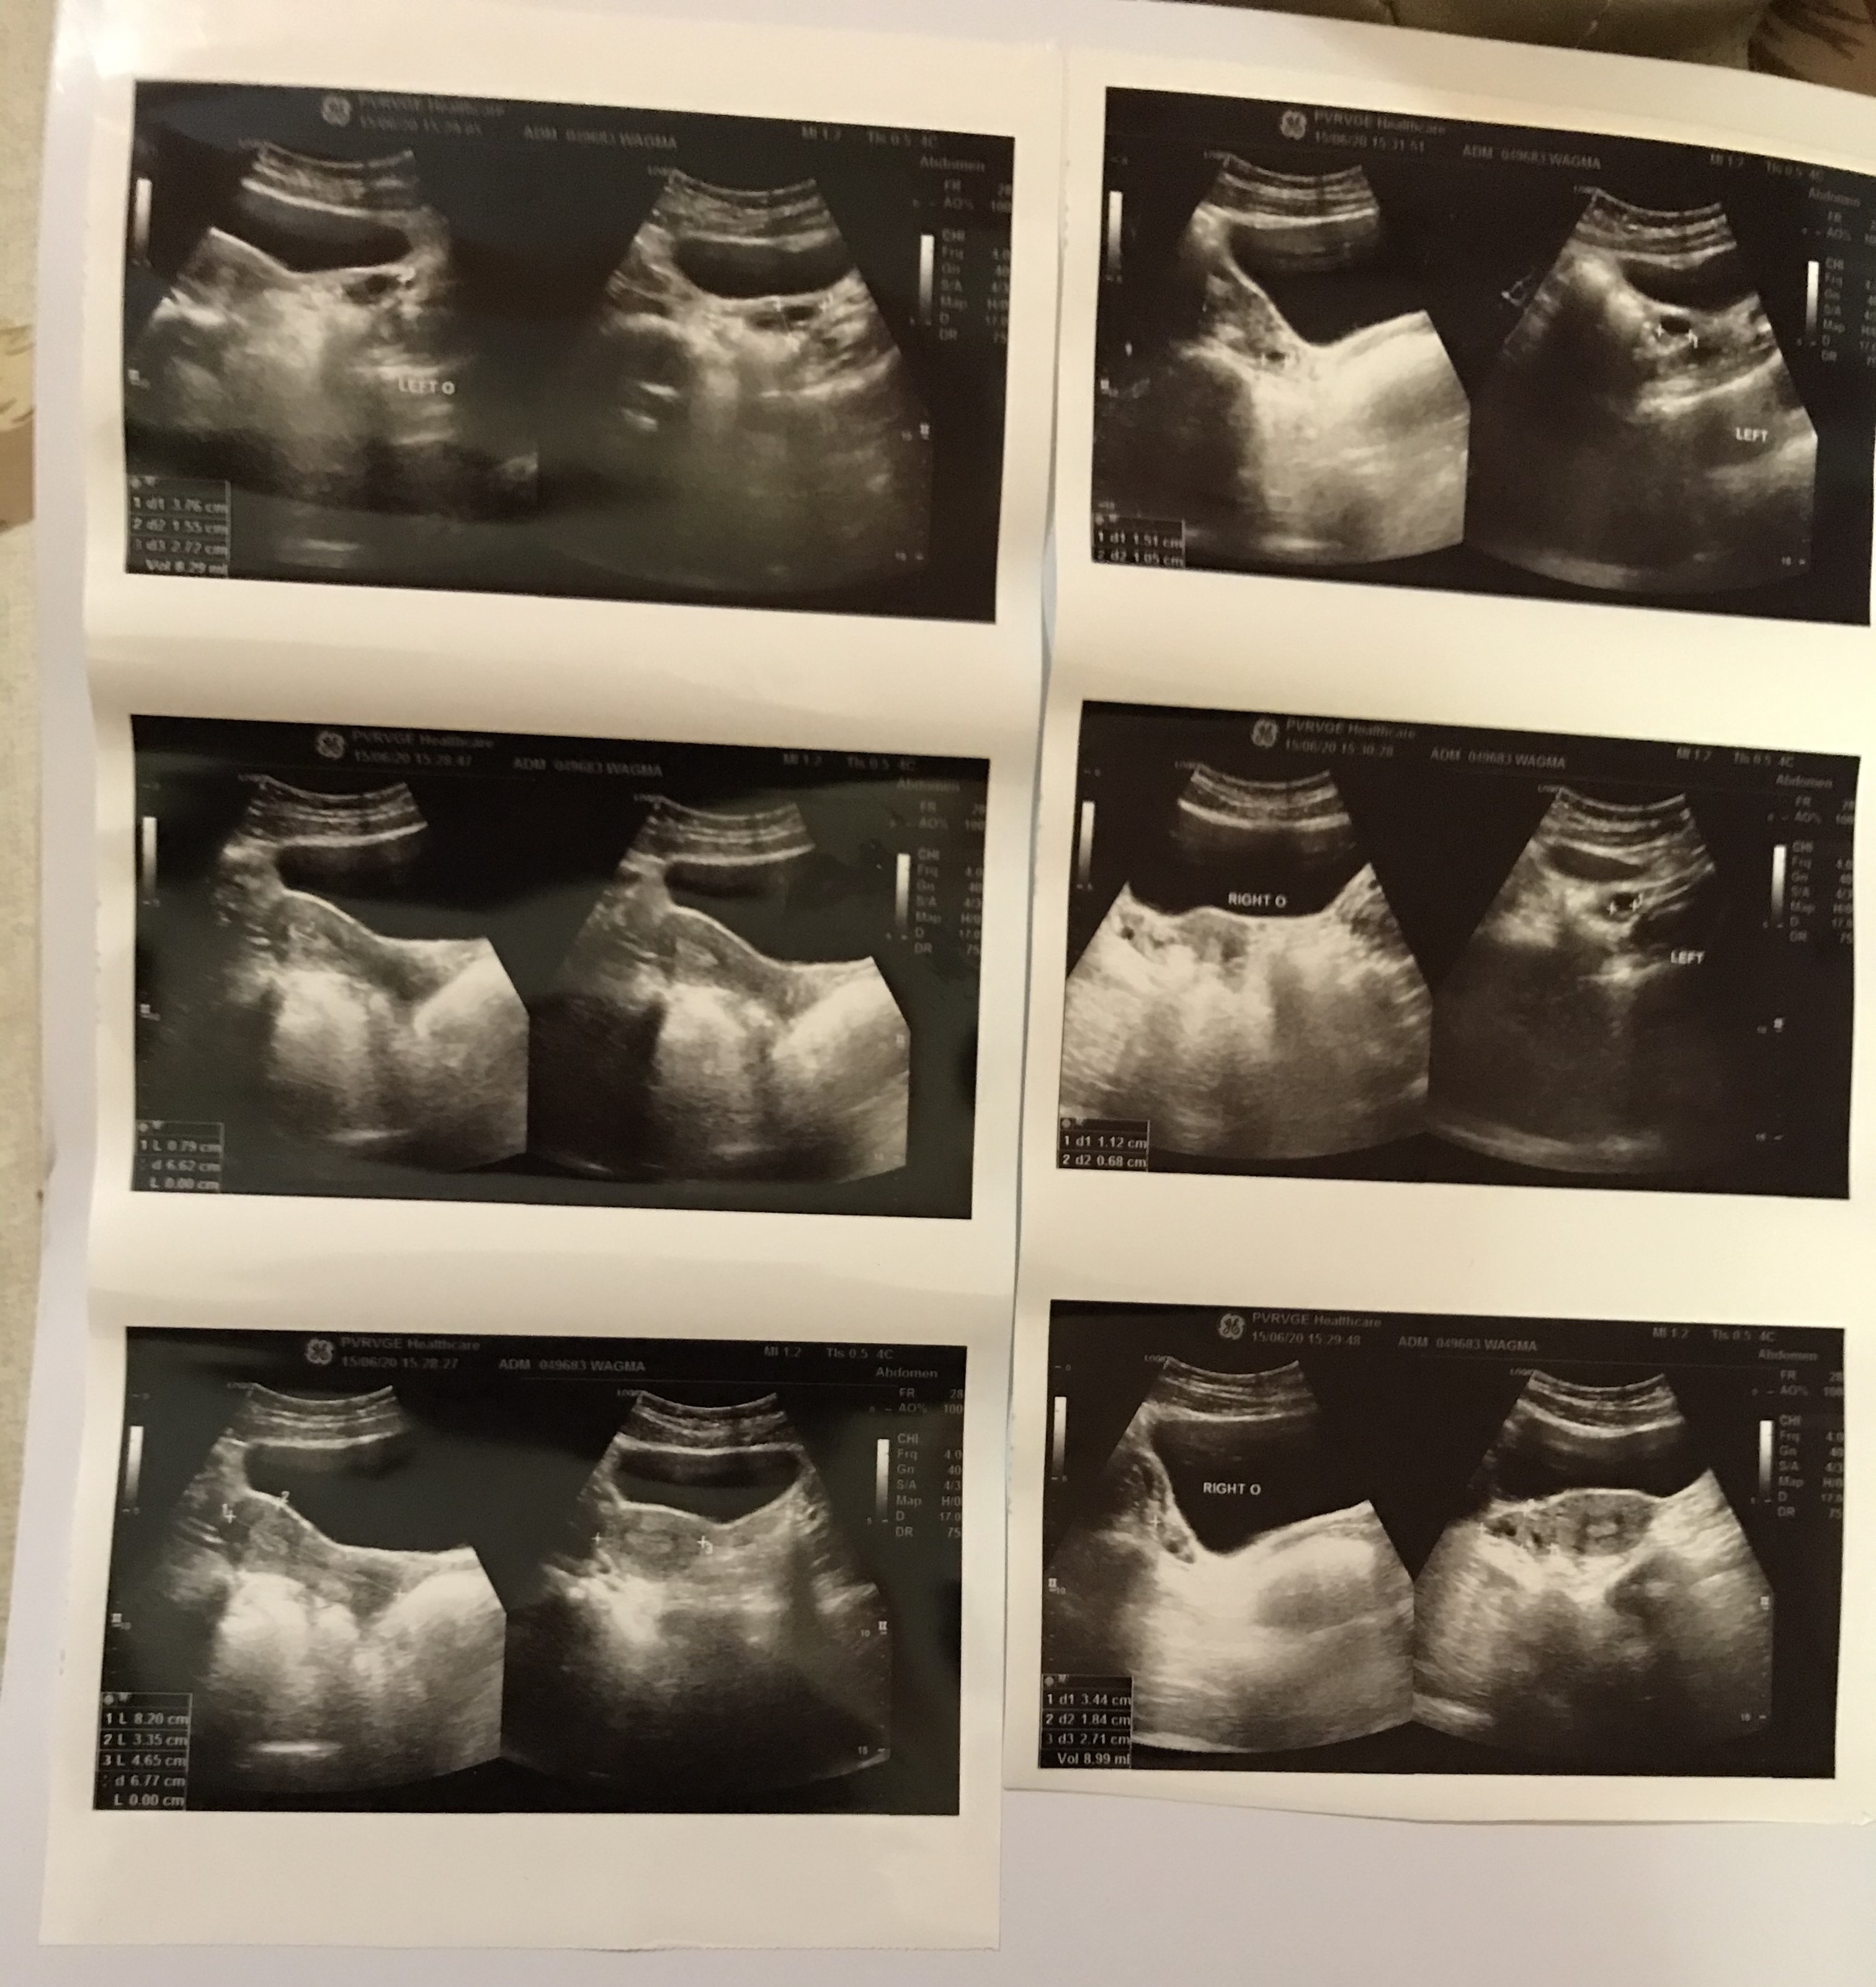

Dr i m attaching my todays pelvic ultrasound report, kindly can u tell me if its fine

#2

#3

#4

Mam i had a pelvic ultrasound just before ramadan .it was a normal ultrasound .

Can pcos emerge in 1-2months?